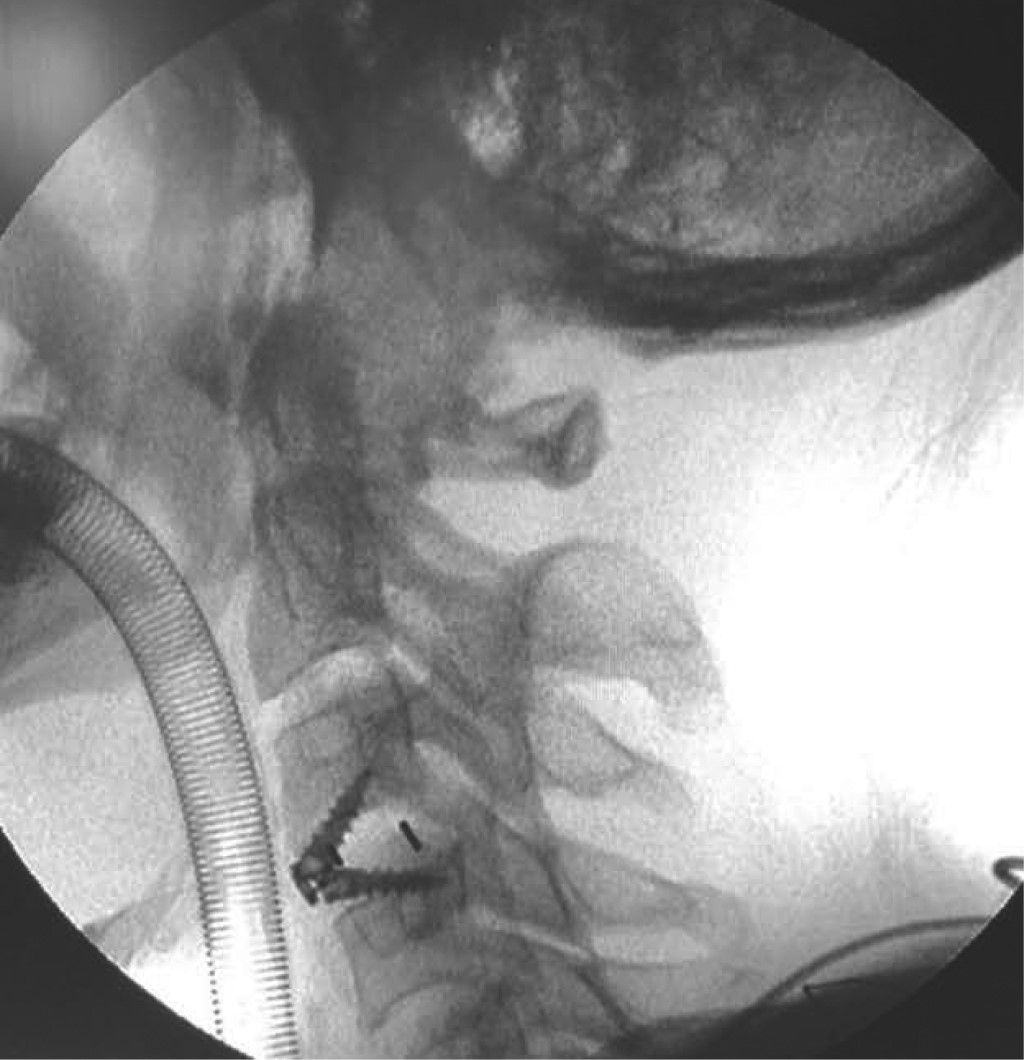

La hernia cervical traumática sin lesión ósea o articular asociada a mielopatía es una patología rara. Los casos reportados en la literatura tuvieron un diagnóstico tardío, secundario a hallazgos clínicos y radiológicos que pueden pasar desapercibidos. Habitualmente, el primer contacto con el paciente no lo realiza un cirujano especialista en columna. Se presenta el caso de un paciente masculino con traumatismo facial, que desarrolló una mielopatía cervical dos semanas después por hernia cervical traumática en C3-C4 sin lesión ósea, que no fue diagnosticada precozmente, posteriormente el paciente presentó alteración neurológica y requirió tratamiento quirúrgico para su descompresión y artrodesis anterior, con buenos resultados a los seis meses de seguimiento.

Figura 3